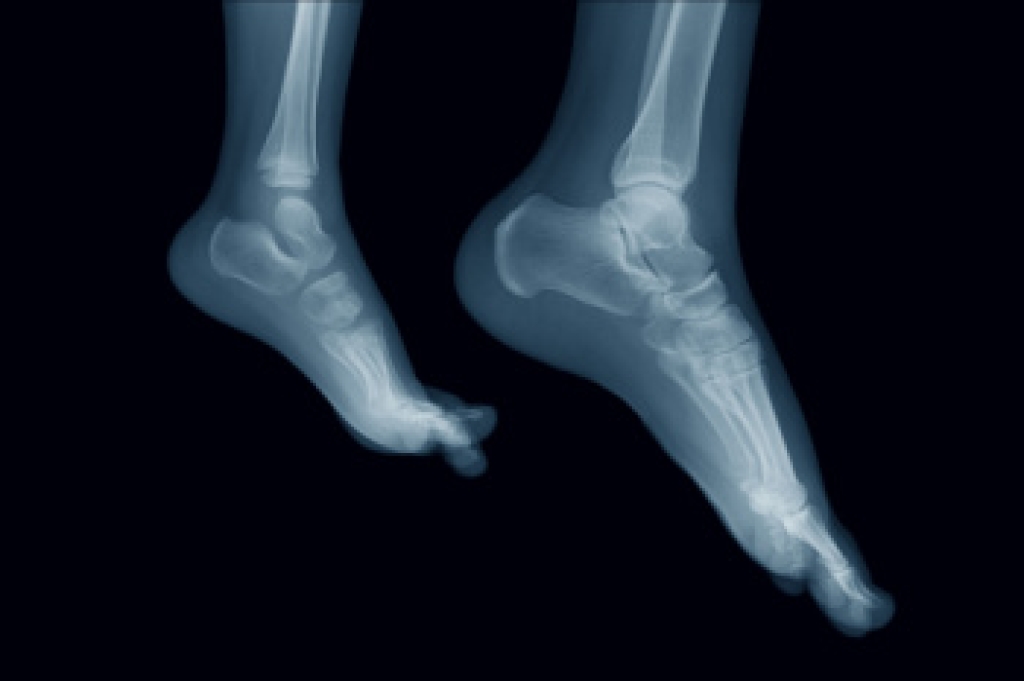

The majority of foot conditions are common and can be treated by a podiatrist. Standard diagnostic procedures are generally used to identify specific conditions and treatment can be rendered. A podiatrist also treats rare foot conditions which can be difficult to diagnose and may need extra attention and care.

Freiberg’s disease - This can be seen as a deterioration and flattening of a metatarsal bone that exists in the ball of the foot. It typically affects pre-teen and teenage girls, but can affect anyone at any age. Symptoms that can accompany this can be swelling, stiffness, and the patient may limp.

Kohler’s disease - This often targets the bone in the arch of the foot and affects younger boys. It can lead to an interruption of the blood supply which ultimately can lead to bone deterioration. The patient may limp or experience tenderness, swelling, and redness.

Maffucci syndrome - This affects the long bones in a child’s foot leading to the development of abnormal bone lesions. They are benign growths and typically develop in early childhood and the bones may be susceptible to breaking.